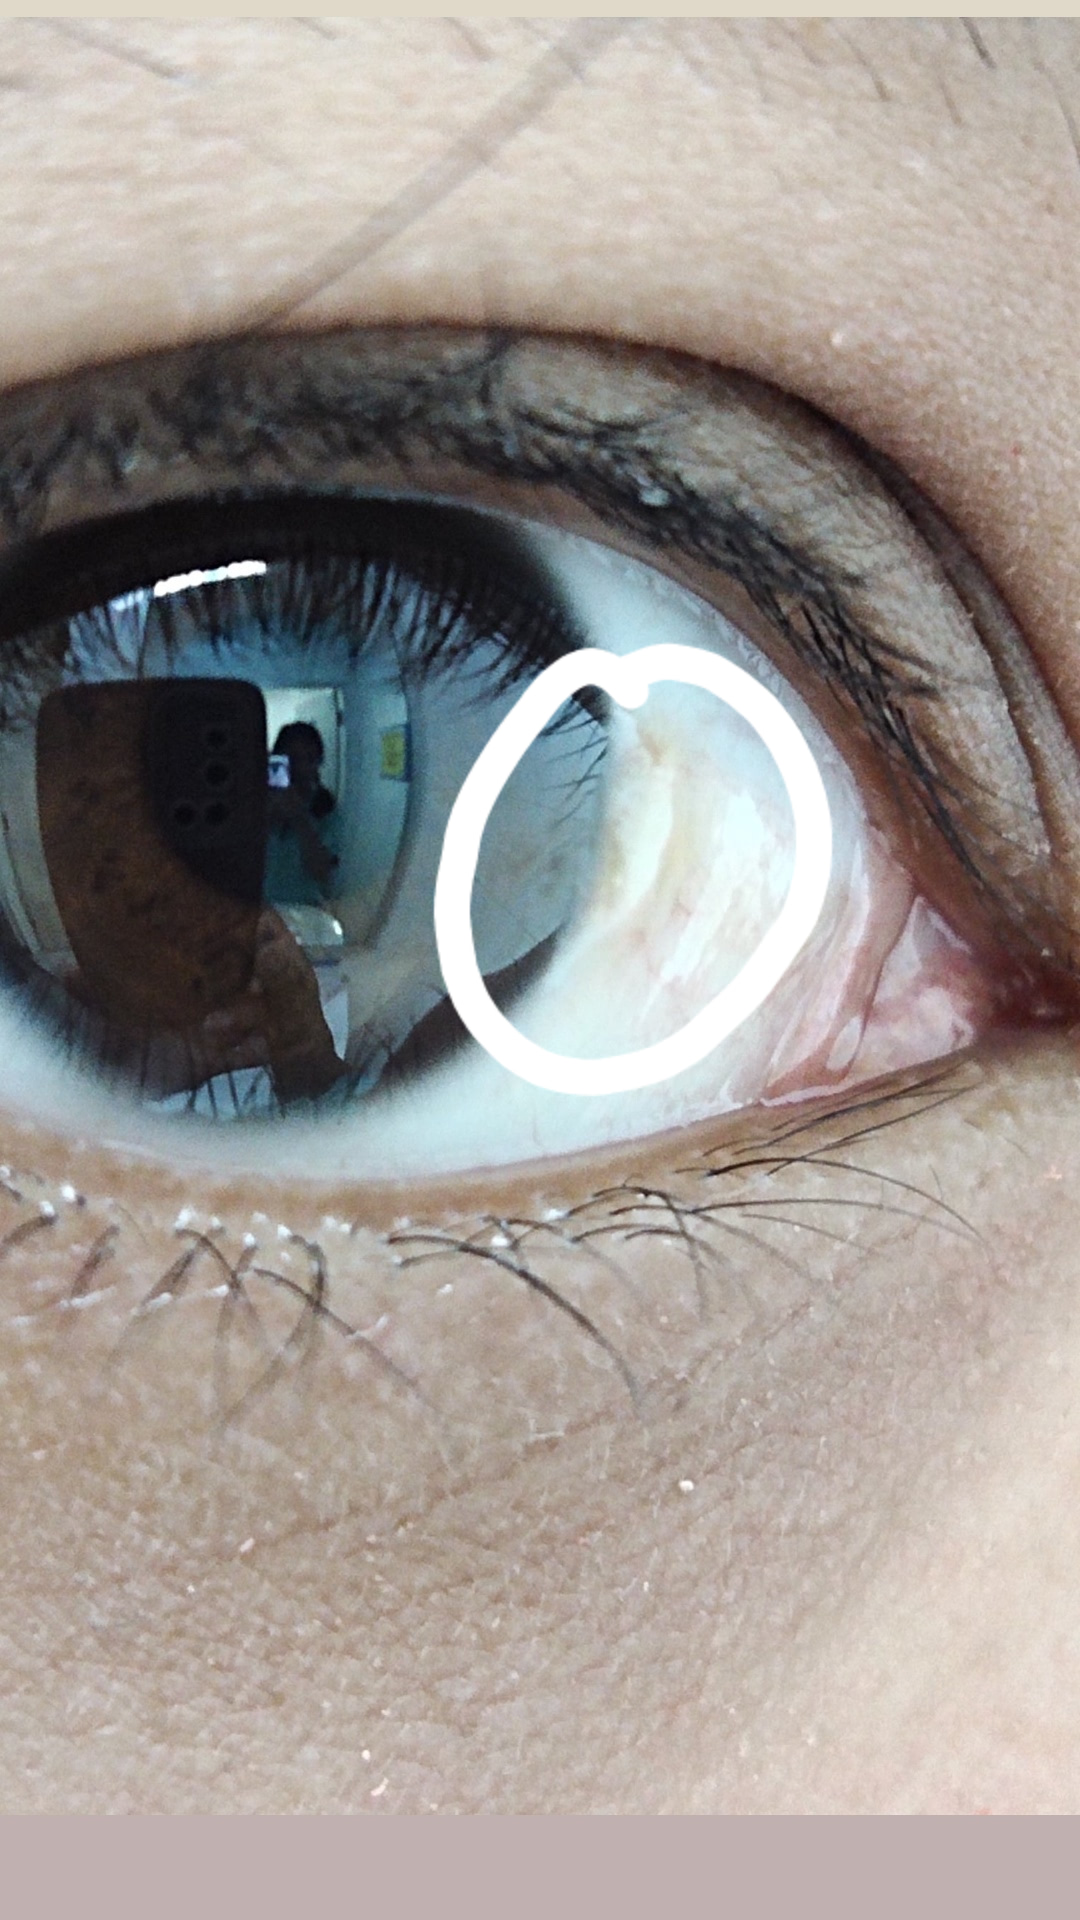

ตาขาวขึ้นเป็นแบบนี้อ่ะ มีใครเป็นมั้ย เกิดจากอะไร วิธีรักษาเบื้องต้น

ต้อลม (Pinguecula) คือภาวะที่เยื่อบุตาขาว (Conjunctiva) เกิดการเสื่อมสภาพ เกิดเป็นก้อนเนื้อนูนขนาดเล็กสีขาว/เหลืองขึ้นบริเวณตาขาว และไม่ลุกลามไปกระจกตาดำ สามารถสร้างความรำคาญให้กับดวงตา เช่น เกิด